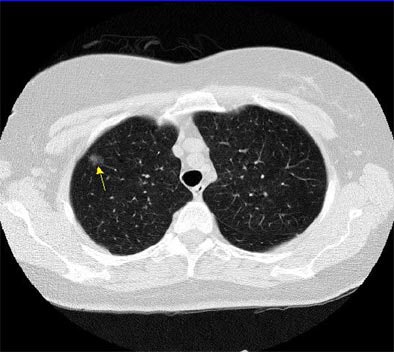

"These part-solid nodules can have linear extensions extending from them, in fact, very consistently. Pathologically they've been shown to correlate with extension of the lymphatic system," he said. "And you can also see this pattern (in) dilated bronchi within these part-solid lesions. It's interesting when you biopsy these, you often get fibrotic material that comes out; you have to be very careful. These tend to be in areas of fibrosis that perhaps causes the dilatation of these bronchi."

![]() |

| Part-solid nodule with linear extensions. All images courtesy of Dr. David Yankelevitz. |